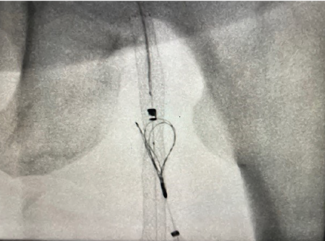

Dr. Tiede describes using a modified gun-sight recanalization approach to reconstruct an absent/occluded common femoral vein in a patient with severe chronic venous disease. A step-by-step discussion of the gun-sight technique is available in...

Matthew A. Tiede, MD